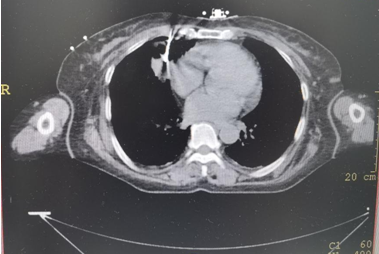

▲上图:IQQA-Guide术中全程三维量化实时定位、跟踪、引导及监控,辅助医生精准穿刺

▲上图:穿刺到位